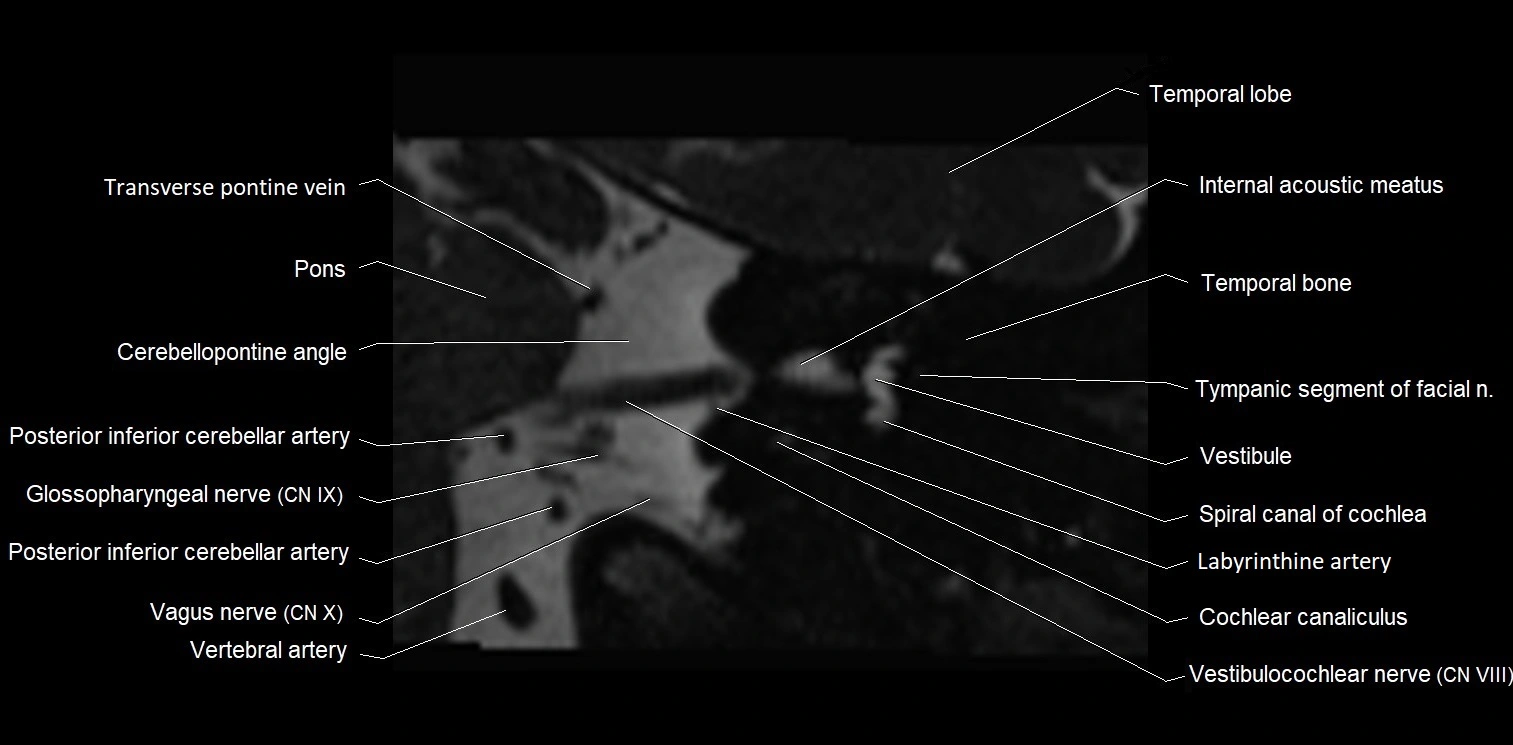

MRI Appearance

• The abducens nerve is a small, thin, linear structure

• Best visualized on high-resolution T2-weighted 3D MRI sequences (e.g., FIESTA or CISS)

• Seen as a hypointense (dark) line running from the brainstem at the pontomedullary junction, traversing the prepontine cistern, and entering Dorello’s canal under the petrosphenoidal ligament, then into the cavernous sinus, and finally the orbit

• May be challenging to visualize in standard MRI due to its small size

• Pathology may be inferred by absence, displacement, or enhancement of the nerve

MRI images

image